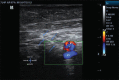

Methods: A total of 150 patients aged 18-75 years, scheduled for simultaneous bilateral total knee replacement, received ultrasound-guided ACB. They were randomised into three groups -Group A received ACB with plain ropivacaine; Groups B and C received ACB with ropivacaine and addition of dexmedetomidine 0.25 μg/kg and 0.50 μg/kg, respectively, on each side of ACB. The primary outcome was the duration of analgesia. Total opioid consumption, success of early ambulation, and level of patient satisfaction were also assessed.